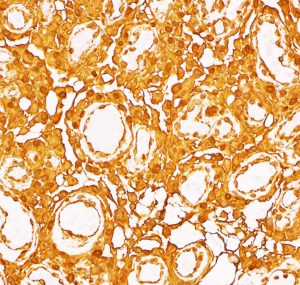

多数の小血管から構成される組織像です。右のvimentin染色は陽性です。

核小体明瞭な大小不同な類円形核からなる細胞境界が不明瞭な腫瘍細胞がみられ,ヘモジデリン貪食マクロファージも認められます。MIB-1染色率は2-3%でグレード1です。